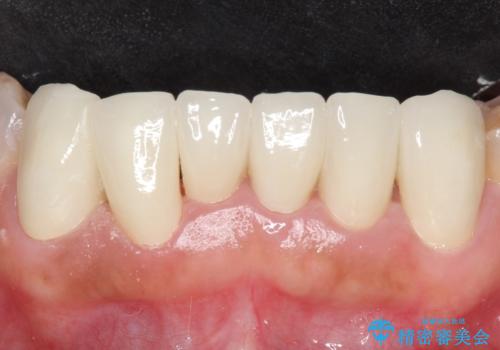

- 上下顎前歯部の見た目が気になるといらっしゃった方の症例です。

上顎は左4番から右4番までの8歯、下顎は左3番から右3番までの6歯、計14歯をオールセラミッククラウンにより補綴しました。

今回用いたオールセラミッククラウンはジルコニアフレームという白い素材の上にセラミックを盛っているため、審美性が非常に高いのが特徴です。

また、ジルコニアは人工ダイヤモンドの材料にも使われているほど高い強度を持っており、そのためオールセラミッククラウンは審美性だけでなく、奥歯やブリッジの補綴も可能とするクラウンです。